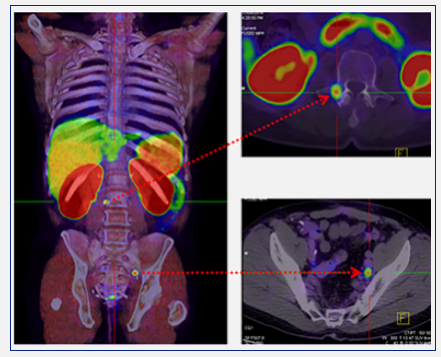

Positron emission tomography–computed tomography (PET-CT) is a global best practice diagnostic imaging tool that captures three-dimensional images of the body's biological functions. By utilising a small amount of a radiotracer (a radioactive substance that is used in medical imaging*), PET-CT scans can detect areas of abnormal metabolism or function in the body, including fast-growing cancers and infections.

PET-CT scans help doctors pinpoint the location of tumours or cancerous lesions, assess the extent of disease, determine whether lesions are benign or malignant, and identify any potential spread.

The PET-CT images